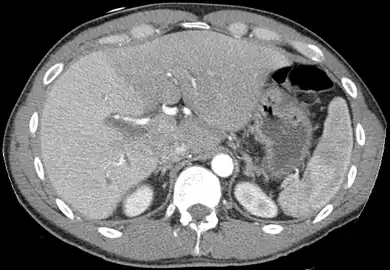

Left lobe liver tumor

The liver is a vital organ and supports almost every other organ in the body. Because of its strategic location and multidimensional functions, the liver is prone to many diseases.[56] The bare area of the liver is a site that is vulnerable to the passing of infection from the abdominal cavity to the thoracic cavity. Liver diseases may be diagnosed by liver function tests–blood tests that can identify various markers. For example, acute-phase reactants are produced by the liver in response to injury or inflammation.